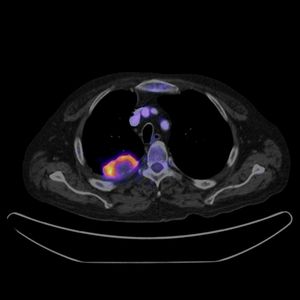

; PET-CT

양전자 방출 단층 촬영(PET) 스캐너와 X선 컴퓨터단층촬영(CT) 스캐너를 단일 갠트리에서 결합한 하이브리드 CT 방식이다.[24] 동일 세션에서 두 장치로부터 순차적 이미지를 획득하여 단일 중첩된(공동 등록된) 이미지로 결합한다. 따라서 신체의 대사 또는 생화학적 활성의 공간적 분포를 나타내는 PET에 의해 획득된 기능적 영상은 CT 스캔에 의해 획득된 해부학적 영상과 보다 정확하게 정렬하거나 상관 관계를 가질 수 있다.[24]

PET-CT는 검사 대상 장기의 해부학적 및 기능적 세부 사항을 모두 제공하며 다양한 유형의 암을 감지하는 데 도움이 된다.[25][26]

3. 6. PET-CT